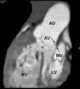

Anatomically corrected malposition of great arteries